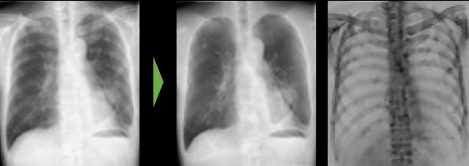

富士フイルム 医療分野における画像処理技術 (一部例)